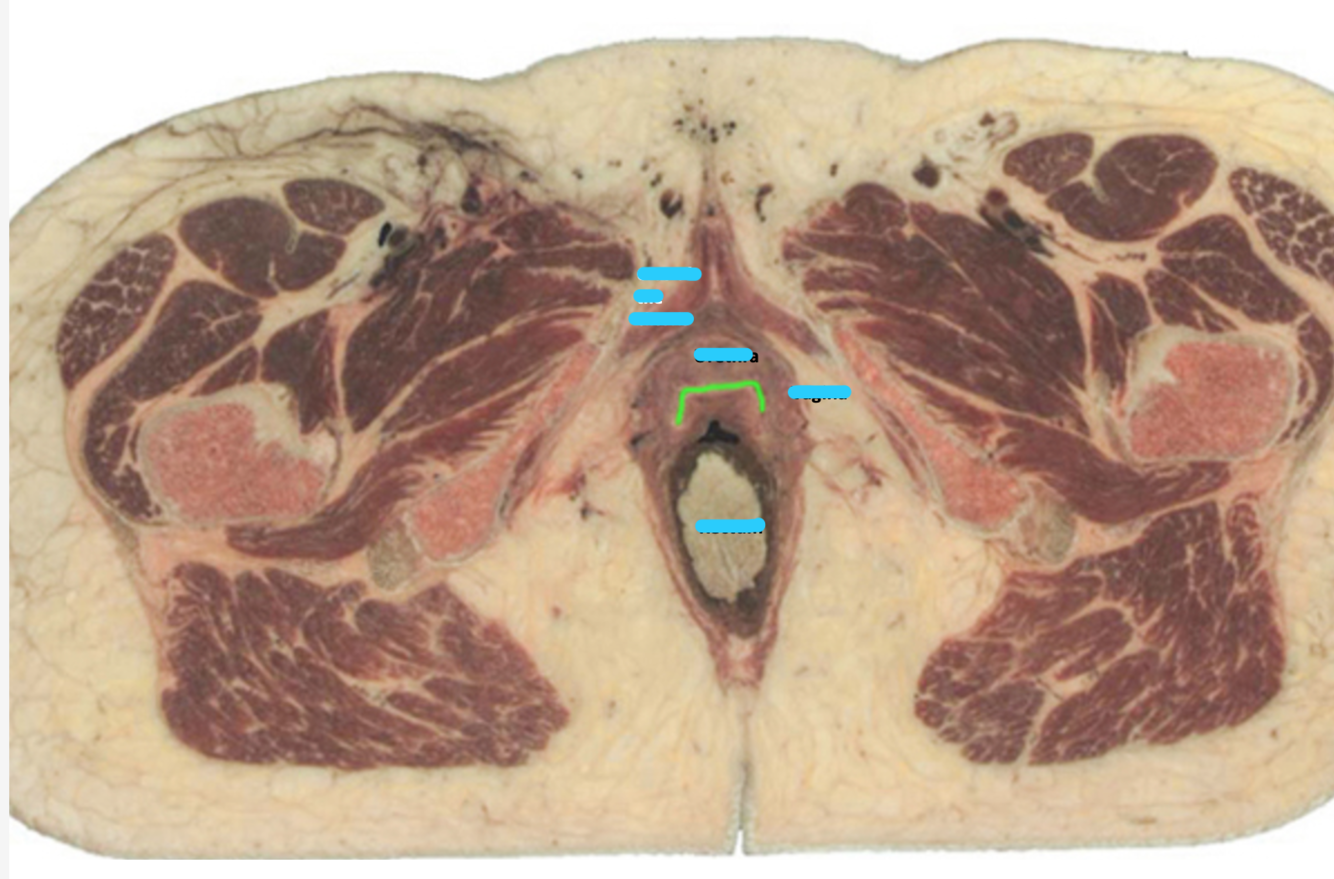

Name the vesicles (blue) and structure (green)